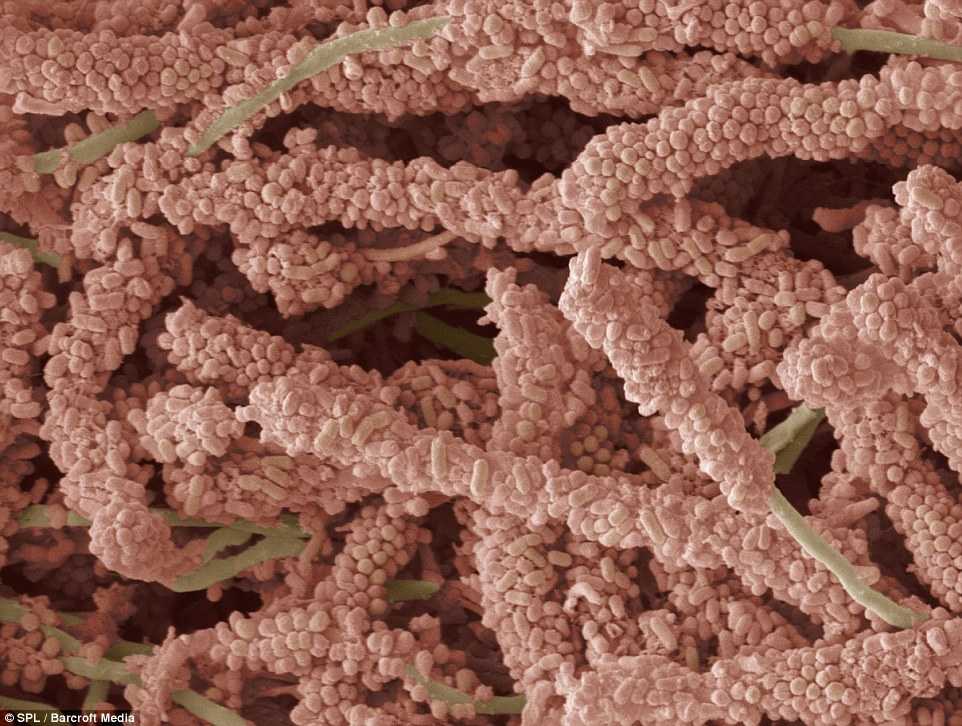

A képen a dentális plakkot alkotó baktériumokat láthatjuk elektronmikroszkóp alatt. ideje megbarátkoznia a gondolattal, hogy a szájban rengeteg baktérium él! Egy részükre nagy szükségünk van: ők segítenek az ételek lebontásában. Az emésztési folyamat ugyanis már a szánkban elkezdődik, majd a gyomorban és a belekben fejeződik be.

A baktériumok a nyállal, elhalt hámsejtekkel és az ételmaradékkal együtt egy vékony réteget, az úgynevezett dentális plakkot képezve rakódnak le a fogainkra.

A gond csak az, hogy a hasznos bacilusok mellett a kártékonyak is elszaporodnak a dentális plakk részeként. Ide soroljuk a fogszuvasodásért és az ínygyulladásért felelős baktériumokat.